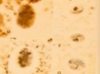

Histomonosis

Histology of Histomoniasis (PAS)